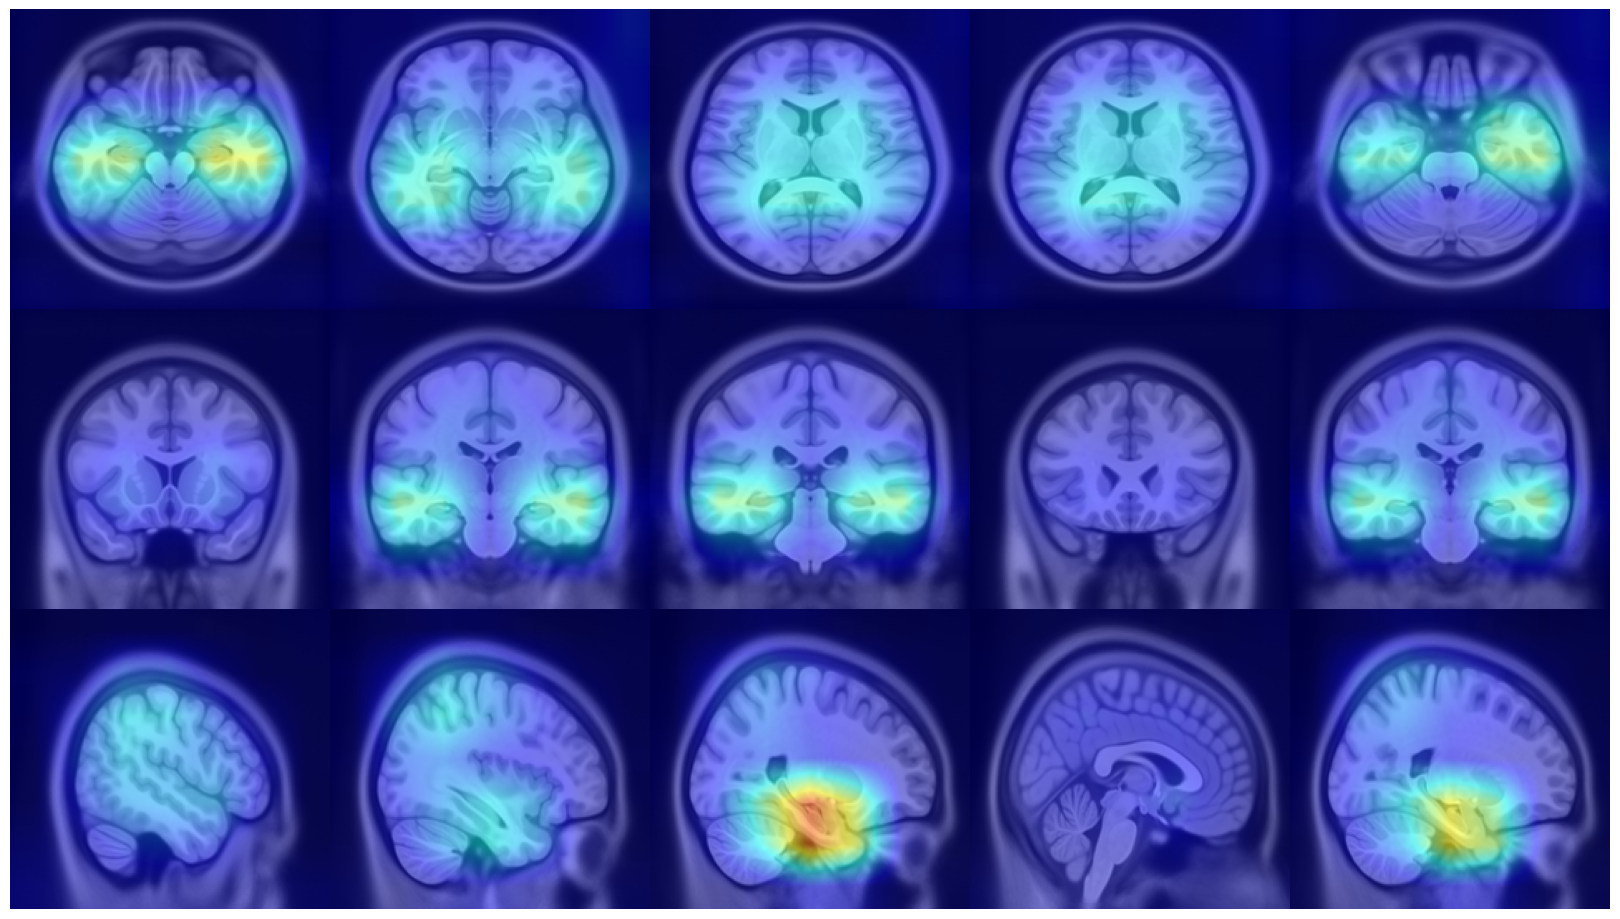

(a) Axial

Refer to caption

(b)

(c) Coronal

(d) Fold 1

(e) Sagittal

(f)

(g)

(h) Fold 2

(i)

(j)

(k) Fold 3

(l)

(m)

(n) Fold 4

(o)

(p)

(q) Fold 5

(r)

Figure 6: Average attention weight distributions generate by AwareNet model for each fold and each plane

We also analyzed the consistencies of AwareNet distributions (Wang et al., 2024) to compare the robustness and interpretability of different attention mechanisms. However, the average distributions produced by this model, as seen in Fig. 6, present sparsely distributed peaks and do not allow the identification of predominant slice ranges. Furthermore, the distributions between the folds are inconsistent. These results indicate that in this case study, AwareNet could not produce consistent attentional weights useful for contributing to the interpretability of its decisions.